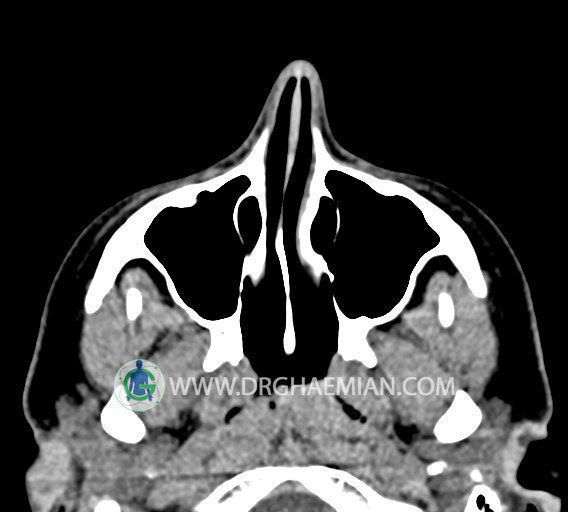

سی تی اسکن سینوس ها یک روش تصویربرداری است که با استفاده از تشعات ایکس تصاویری با جزییات از ناحیه خالی داخل صورت (سینوس ها) ایجاد میکند. در این کیس استئوم فرعی سینوس در دیواره سینوس ماگزیلاری، انحراف سپتوم و کونکا بولوزا مشاهده می شود.

در HRCT اسپيرال از سينوس هاي پارانازال مقاطع کرونال و آگزيال ( 16 اسلايس و مقاطع ظريف 1.5 mm بدون فاصله ، با پنجره استخواني و نسج نرم ) :

– انحراف سپتوم مياني بينی به راست

– کونکا بولوزا در کونکای ميانی چپ و

– اوستيوم فرعي در ديواره مديال سينوس ماگزيلاري راست

مشهود است .